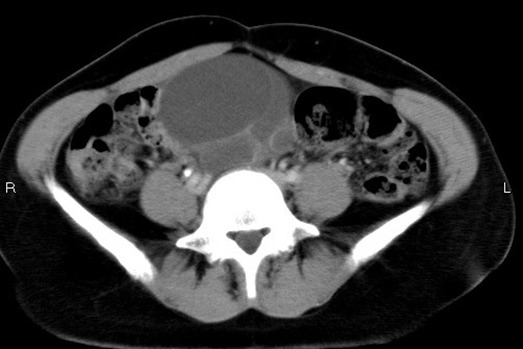

妊娠反応は陰性でしたが、異所性妊娠を念頭に腹水をチェック(認めませんでした)。下腹部に嚢胞性の腫瘤が描出され、皆さんからの回答で最多だった卵巣茎捻転がますます疑わしくなりました。commonな疾患として、尿路結石やイレウスも頭に浮かびますが、水腎症やto and fro movementの欠如は明らかではありませんでした。その後、他疾患の除外+確定診断のため、腹部造影CTを行っています。

画像の通り、卵巣腫瘤(7cm×9㎝程)を認め、経過から茎捻転を疑い産婦人科にコンサルト。緊急手術となり、左卵巣嚢腫茎捻転と確定診断されました。(左の卵巣が180度捻じれていたそうです。)